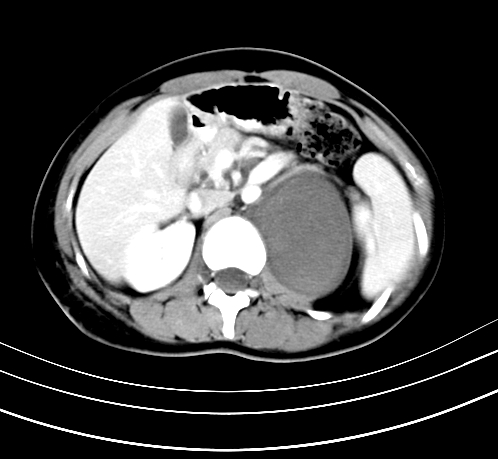

静脉期